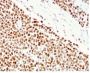

Positive Control

HCT116 or HeLa cell lysate (WB). Human colon carcinoma (IHC).

Antibody target cellular localization

Nucleus